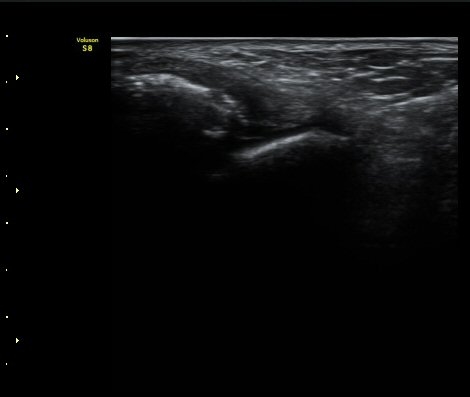

¹ß¸ñ°üÀý Á¾´Ü¸é°Ë»ç¿¡¼­ °üÀý³» ¼ö¾×Àú·ù°¡ °üÂûµÈ´Ù(±×¸² 1).

Àü°Å°ñºñ°ñÀδë Á¾´Ü¸é°Ë»ç»ó Àδë ÀδëÀÇ Àú¿¡ÄÚ ºÎÁ¾°ú ºñ°ñ

ºÎÂøºÎ ¹Ì¼¼ °ß¿­°ñÀýÀÌ °üÂûµÈ´Ù(±×¸² 3, 4).

ÃÊÀ½ÆÄÅõ½ÃÇÏ ºÎÇϰ˻翡¼­ ºñ°ñ°ú °ß¿­°ñÀý °ñÆí»çÀÌ¿Í ºñ°ñ°ú °Å°ñ »çÀ̰¡ ¹ú¾îÁø´Ù

(樨毢 1)